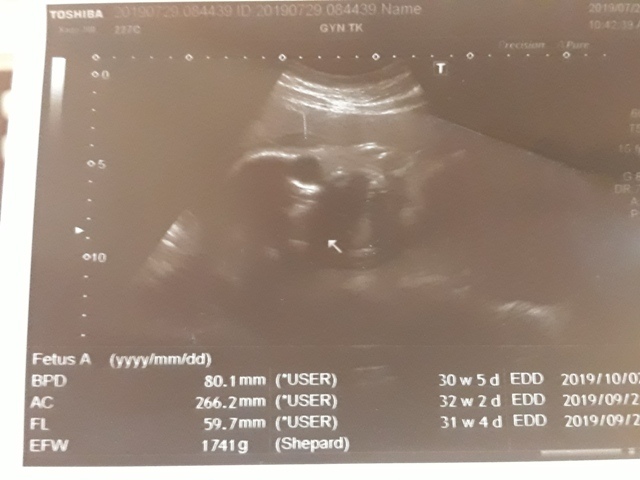

| 仙人掌(2019/07/29)的真心話 星期一 天氣晴 編號19-199 |

近八次產檢資料統計↓

| 2019年07月29日 | 80.1mm (8%) | 266.2mm (10%) | 59.7mm (10%) | 1741g (32%) | 136 |

| BPD:胎兒頭骨橫徑 AC:胎兒腹圍的長度 FL:胎兒大腿骨的長度 EFW:胎兒的體重 括弧內百分比為較上次產檢的成長比例 | |||||